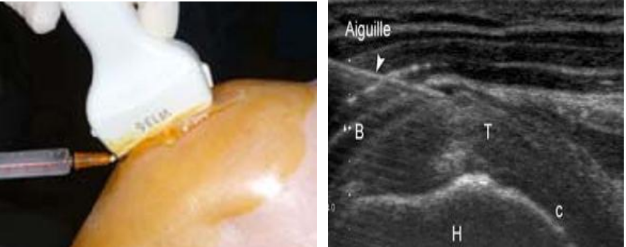

- Siêu âm xác định vị trí cần tiêm: đặt đầu dò ở lát cắt dọc qua gân cơ trên gai

- Tiến hành chọc kim qua da tiến sát tới bao gân cơ trên gai, hướng kim đi song song với đầu dò và vuông góc với chùm tia siêu âm và đồng thời với quan sát trên màn hình, tới vị trí gân cơ trên gai thì tiến hành tiêm thuốc

Hình minh họa: Tiêm gân trên gai dưới hướng dẫn của siêu âm. Nguồn: internet.